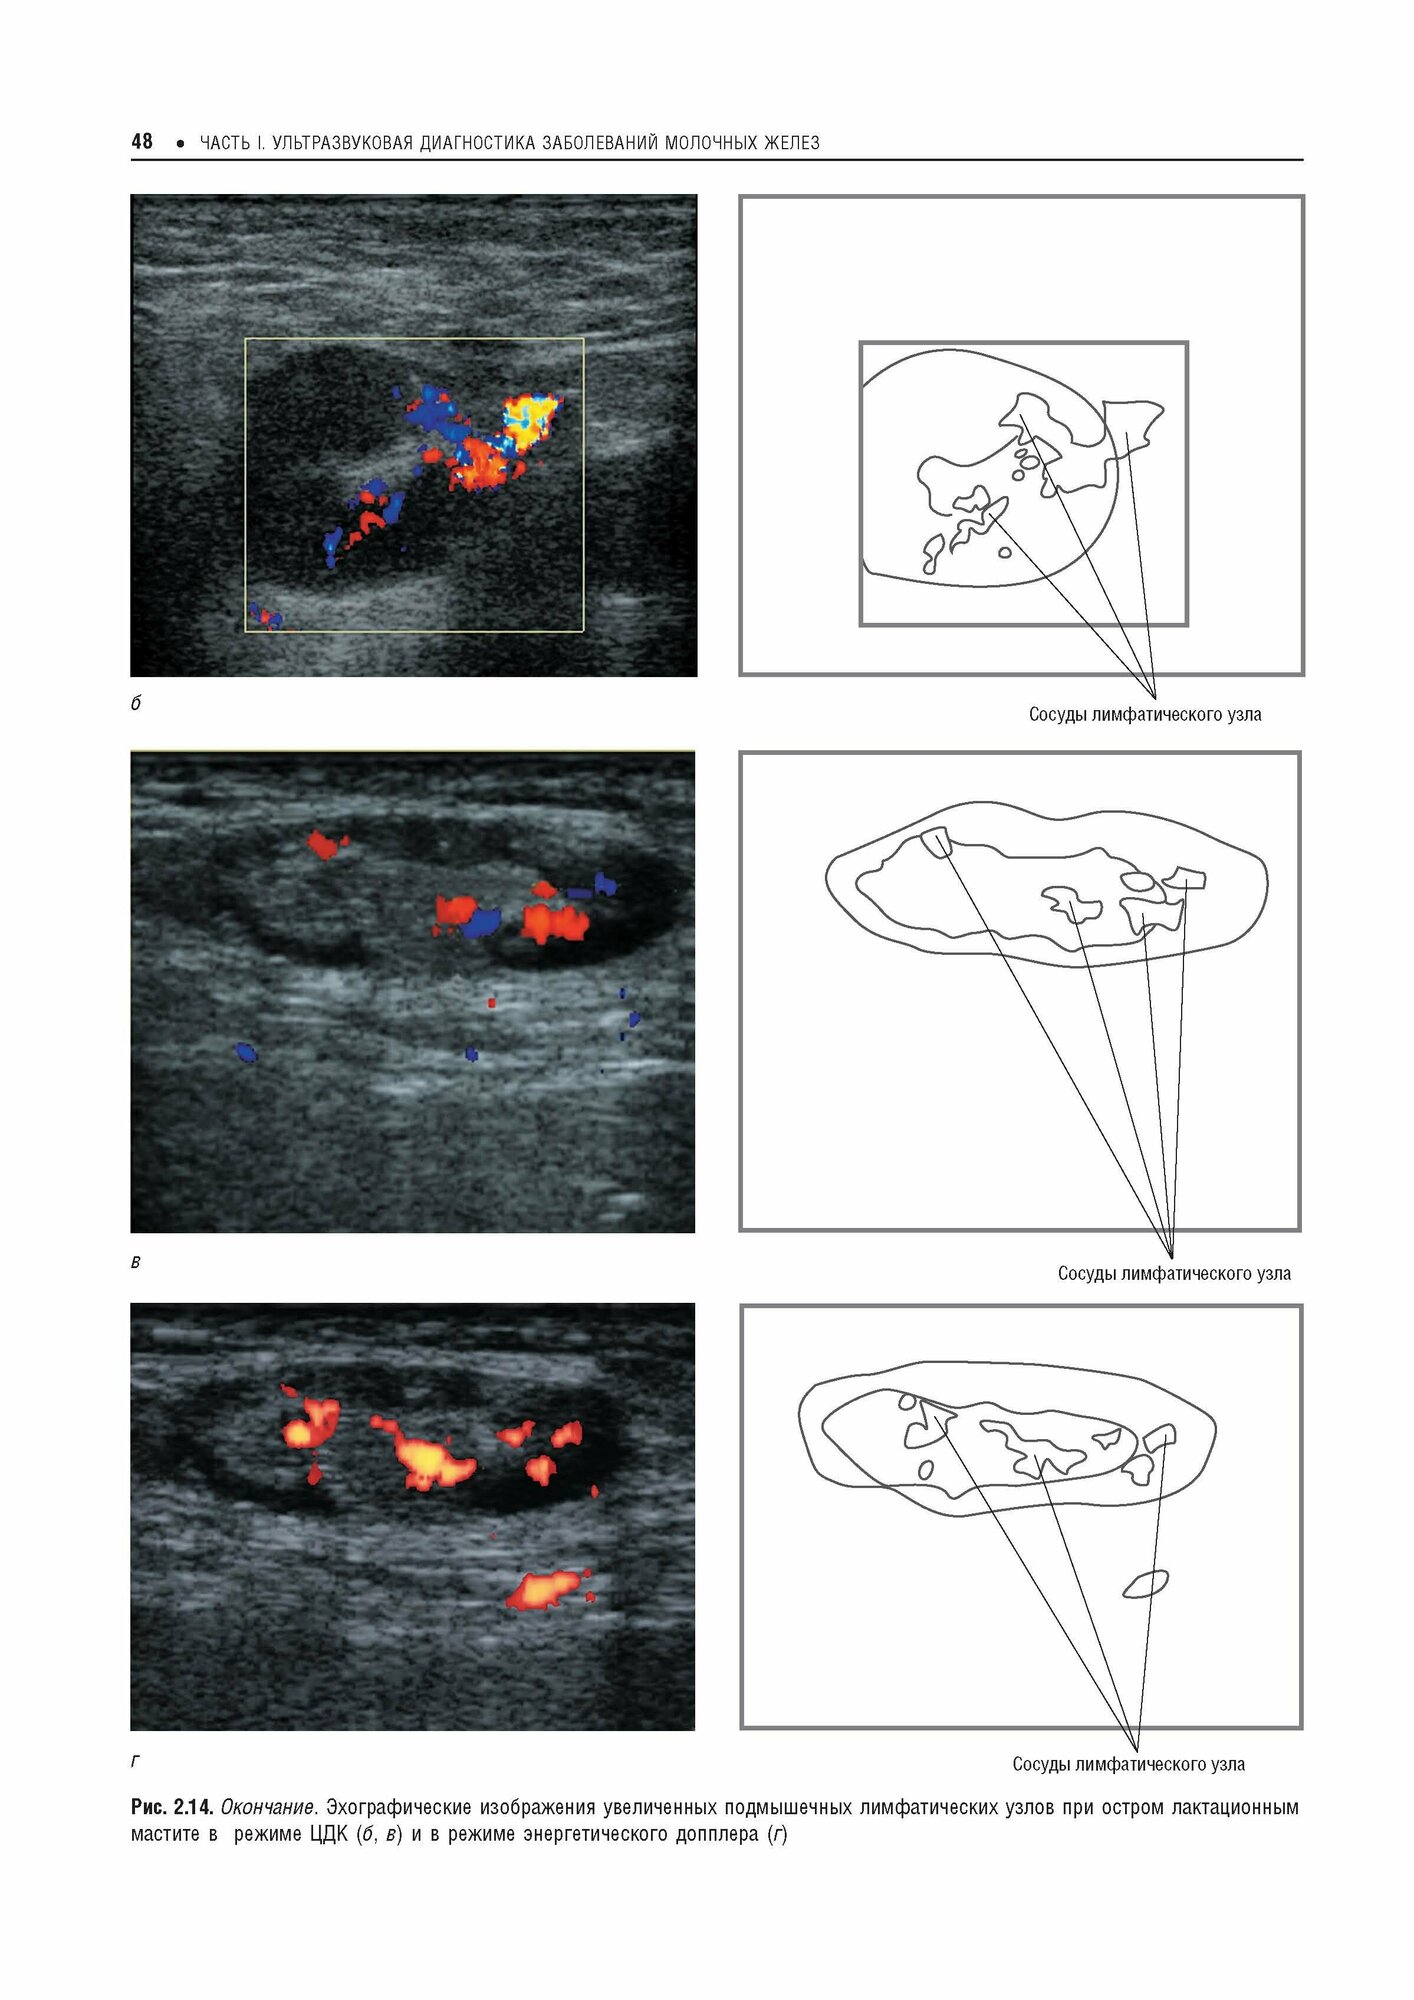

Практическая ультразвуковая диагностика. Руководство для врачей в пяти томах. Том 5. Ультразвуковая диагностика заболеваний молочных желез и мягких тканей (Труфанов Геннадий Евгеньевич, Иванова Людмила Игоревна, Вецмадян Елена Анатольевна); ГЭОТАР-Медиа, 2017

Пятый том руководства посвящен использованию различных методик ультразвукового исследования в диагностике заболеваний молочных желез и мягких тканей.

.Первая часть книги посвящена ультразвуковым исследованиям молочных желез. Описаны нормальная ультразвуковая анатомия, клинические особенности и ультразвуковая семиотика наиболее часто встречающихся заболеваний и патологий. Отдельная глава дает обзор методов и методик компрессионной эластографии в маммологии.